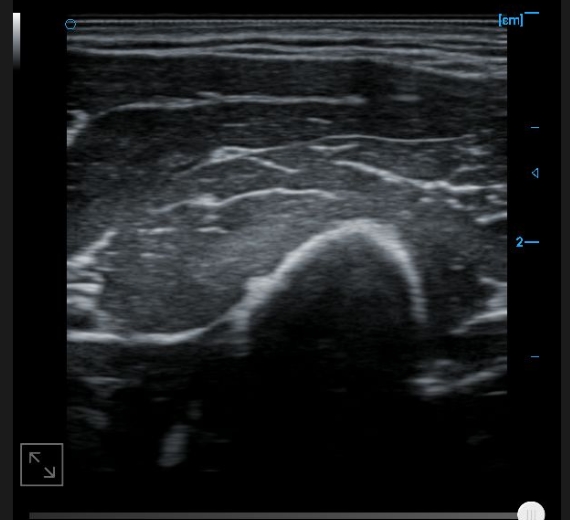

Patellar tendon B image

B-image of quadriceps tendon

Knee collateral ligament B image

B-image of femoral trochlear cartilage